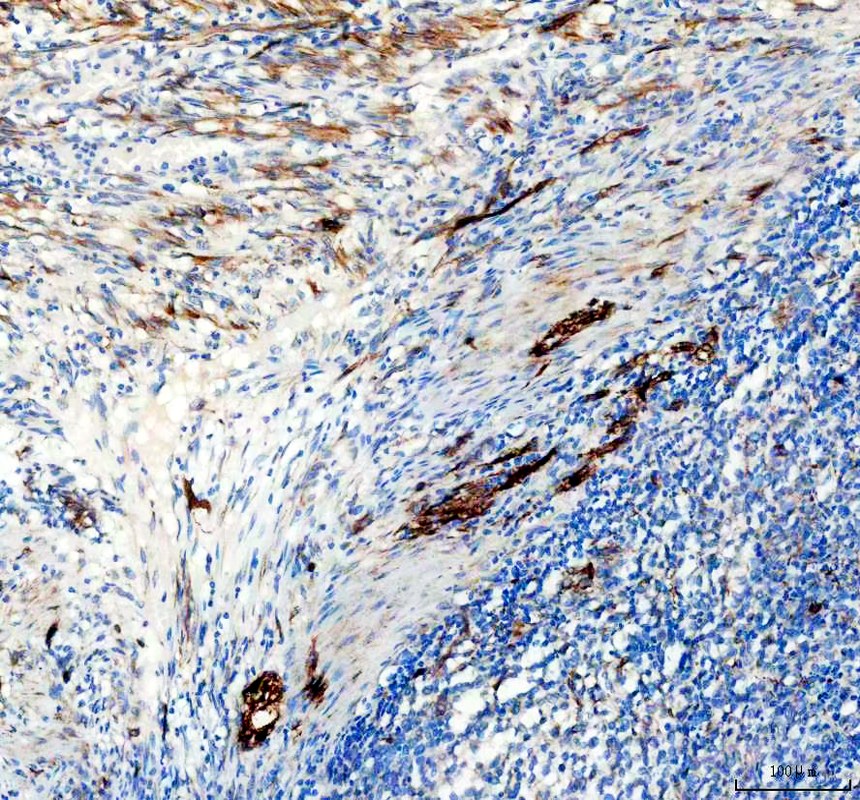

IHC analysis of Nestin/NES using anti-Nestin/NES antibody (BM4494).

Nestin/NES was detected in a paraffin-embedded section of human Diffuse large B-cell lymphoma of the intestine tissue. The tissue section was incubated with rabbit anti-Nestin/NES Antibody (BM4494) at a dilution of 1:200 and developed using HRP Conjugated Rabbit IgG Super Vision Assay Kit (Catalog # SV0002) with DAB (Catalog # AR1027) as the chromogen.